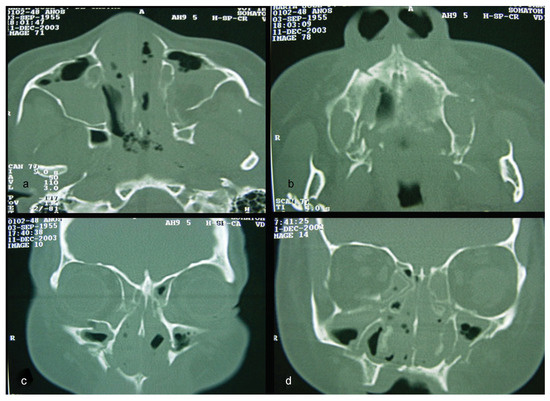

Figure 2.

(a–d) CT windows displaying multiple fractures in the middle third of the face or midface.